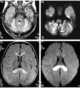

Neuroaxonal dystrophy

Infantile neuroaxonal dystrophy is a rare pervasive developmental disorder that primarily affects the nervous system. Individuals with infantile neuroaxonal dystrophy typically do not have any symptoms at birth, but between the ages of about 6 and 18 months they begin to experience delays in acquiring new motor and intellectual skills, such as crawling or beginning to speak. [Source: Wikipedia ]